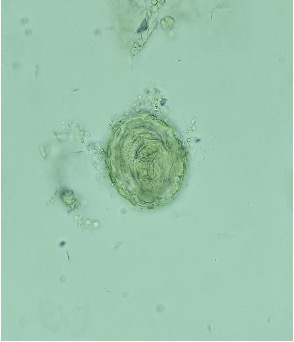

Esquizonte maduro com um elevado número de Merozoítos

Não é possível a visualização das granulações de Schuffner no eritrócito parasitado pois este está quase a arrebentar.

Os Esquizontes jovens e maduros geralmente não aparecem no sangue periférico no Plasmodium falciparum. No entanto, se houver uma Parasitemia muito elevada (que não é o caso da imagem) estas formas desta espécie podem aparecer no sangue periférico.

→ Esquizonte maduro de Plasmodium vivax!